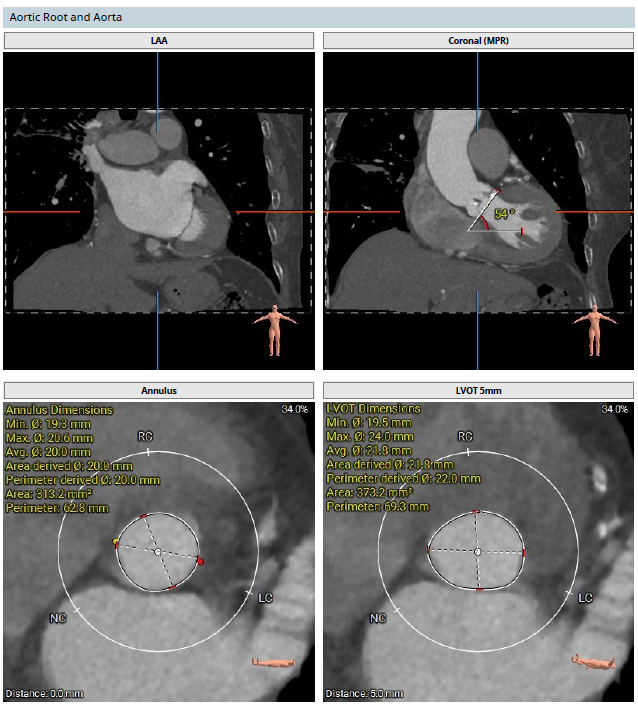

术前CT检查

该患者术前CT分析瓣环20.0mm,流出道22.0mm, Type0型二叶瓣,瓣叶轻中度钙化并增厚,瓣膜锚定力可,流出道直筒偏敞口,预估瓣膜释放后位移风险低,少量瓣周漏可能;

冠脉开口高度可,右冠瓣冗长瓣叶,预估冠脉阻挡风险低术中密切关注冠脉血流灌注,必要时冠脉保护;